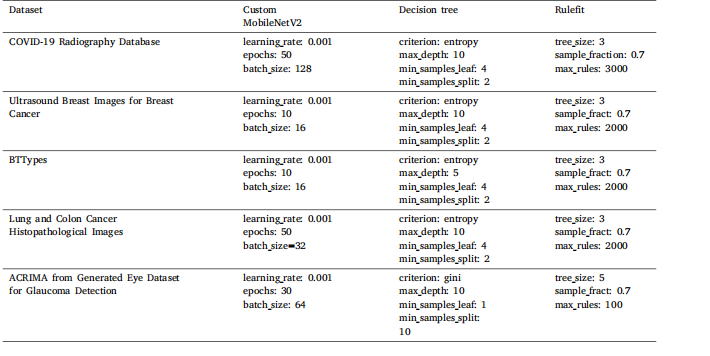

Table 2Hyperparameters values for each model used in grid search optimization

Table 5Summary of the optimized hyperparameters on each dataset.

表5 每个数据集上优化后的超参数摘要。